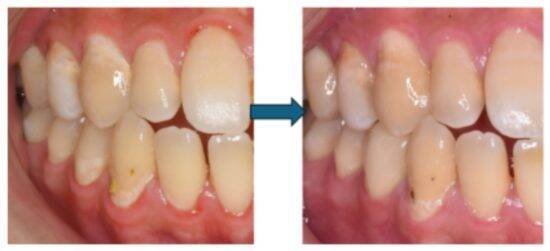

久しぶりにフロスを通して出血したり嫌な臭いがしても驚かないでください。それは歯茎が炎症しているサインです。毎日ケアをし続けることで、早ければ1~2週間で炎症が治まり、出血はなくなり、臭いも消え、引き締まった健康的なピンク色の歯茎に戻ります。もし、治りが悪い場合はすぐに歯科医院で相談をしましょう。